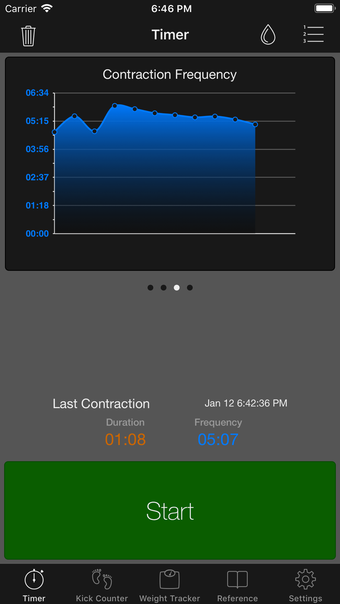

이 어플리케이션은 조기 분만을 겪는 여성들이 분만 과정을 지속적으로 추적할 필요가 있는 경우에 디자인되었습니다. 기능성을 희생하지 않고 사용자 친화적인 어플리케이션을 만들고자 했습니다.

이 어플리케이션은 분만 진행 상황을 명확하게 보여주며, 현재 분만 단계, 이전 및 현재 수축의 시작 및 종료 시간을 보여줍니다. Full Term은 수동으로 각 수축을 시작하고 중지할 필요가 없으며, 어플리케이션을 재시작하더라도 분만 기록을 추적합니다.